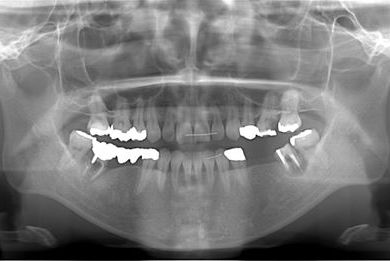

| 治療方針 | 抜歯と同時にインプラント治療を行い、治療期間を短縮する。 | ||||||||||||||||||||||||||||||||

| 治療内容 | インプラント4本(抜歯即日スピードインプラント治療)、ハイブリッドセラミッククラウン6本 | ||||||||||||||||||||||||||||||||

| 総治療費 | 1,236,165円 | ||||||||||||||||||||||||||||||||

| 治療期間 | 1年5ヶ月 |